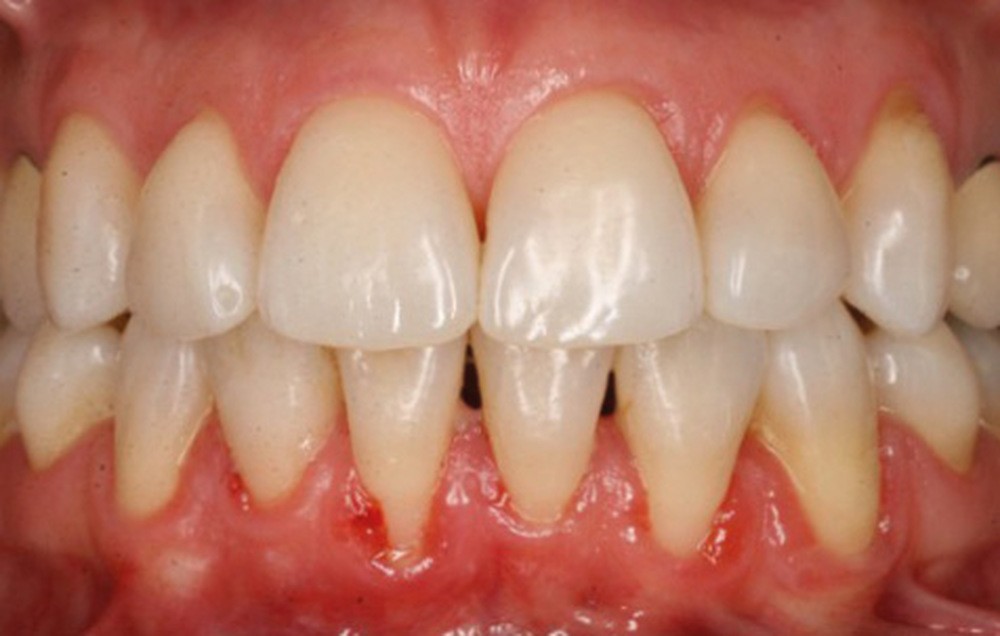

Quelle insatisfaction et quelle déception de constater, en cours ou à l’issue d’un traitement orthodontique, la fragilisation du parodonte, voire l’apparition d’une récession gingivale !

C’est à ces questions que nous permettront de répondre les deux premiers conférenciers, parodontologistes : le Dr Béatrice Straub nous présentera le renfort parodontal minéralisé, technique qu’elle a développée et pratique depuis de nombreuses années, pour éviter les préjudices des mouvements orthodontiques à risque, notamment lors des décompensations préchirurgicales (fig. 1a-d) ; le Pr Anton Sculean abordera le thème des greffes, avec leurs indications, les différentes techniques à privilégier et illustrera ses propos par de nombreux cas cliniques aux résultats esthétiques impressionnants.